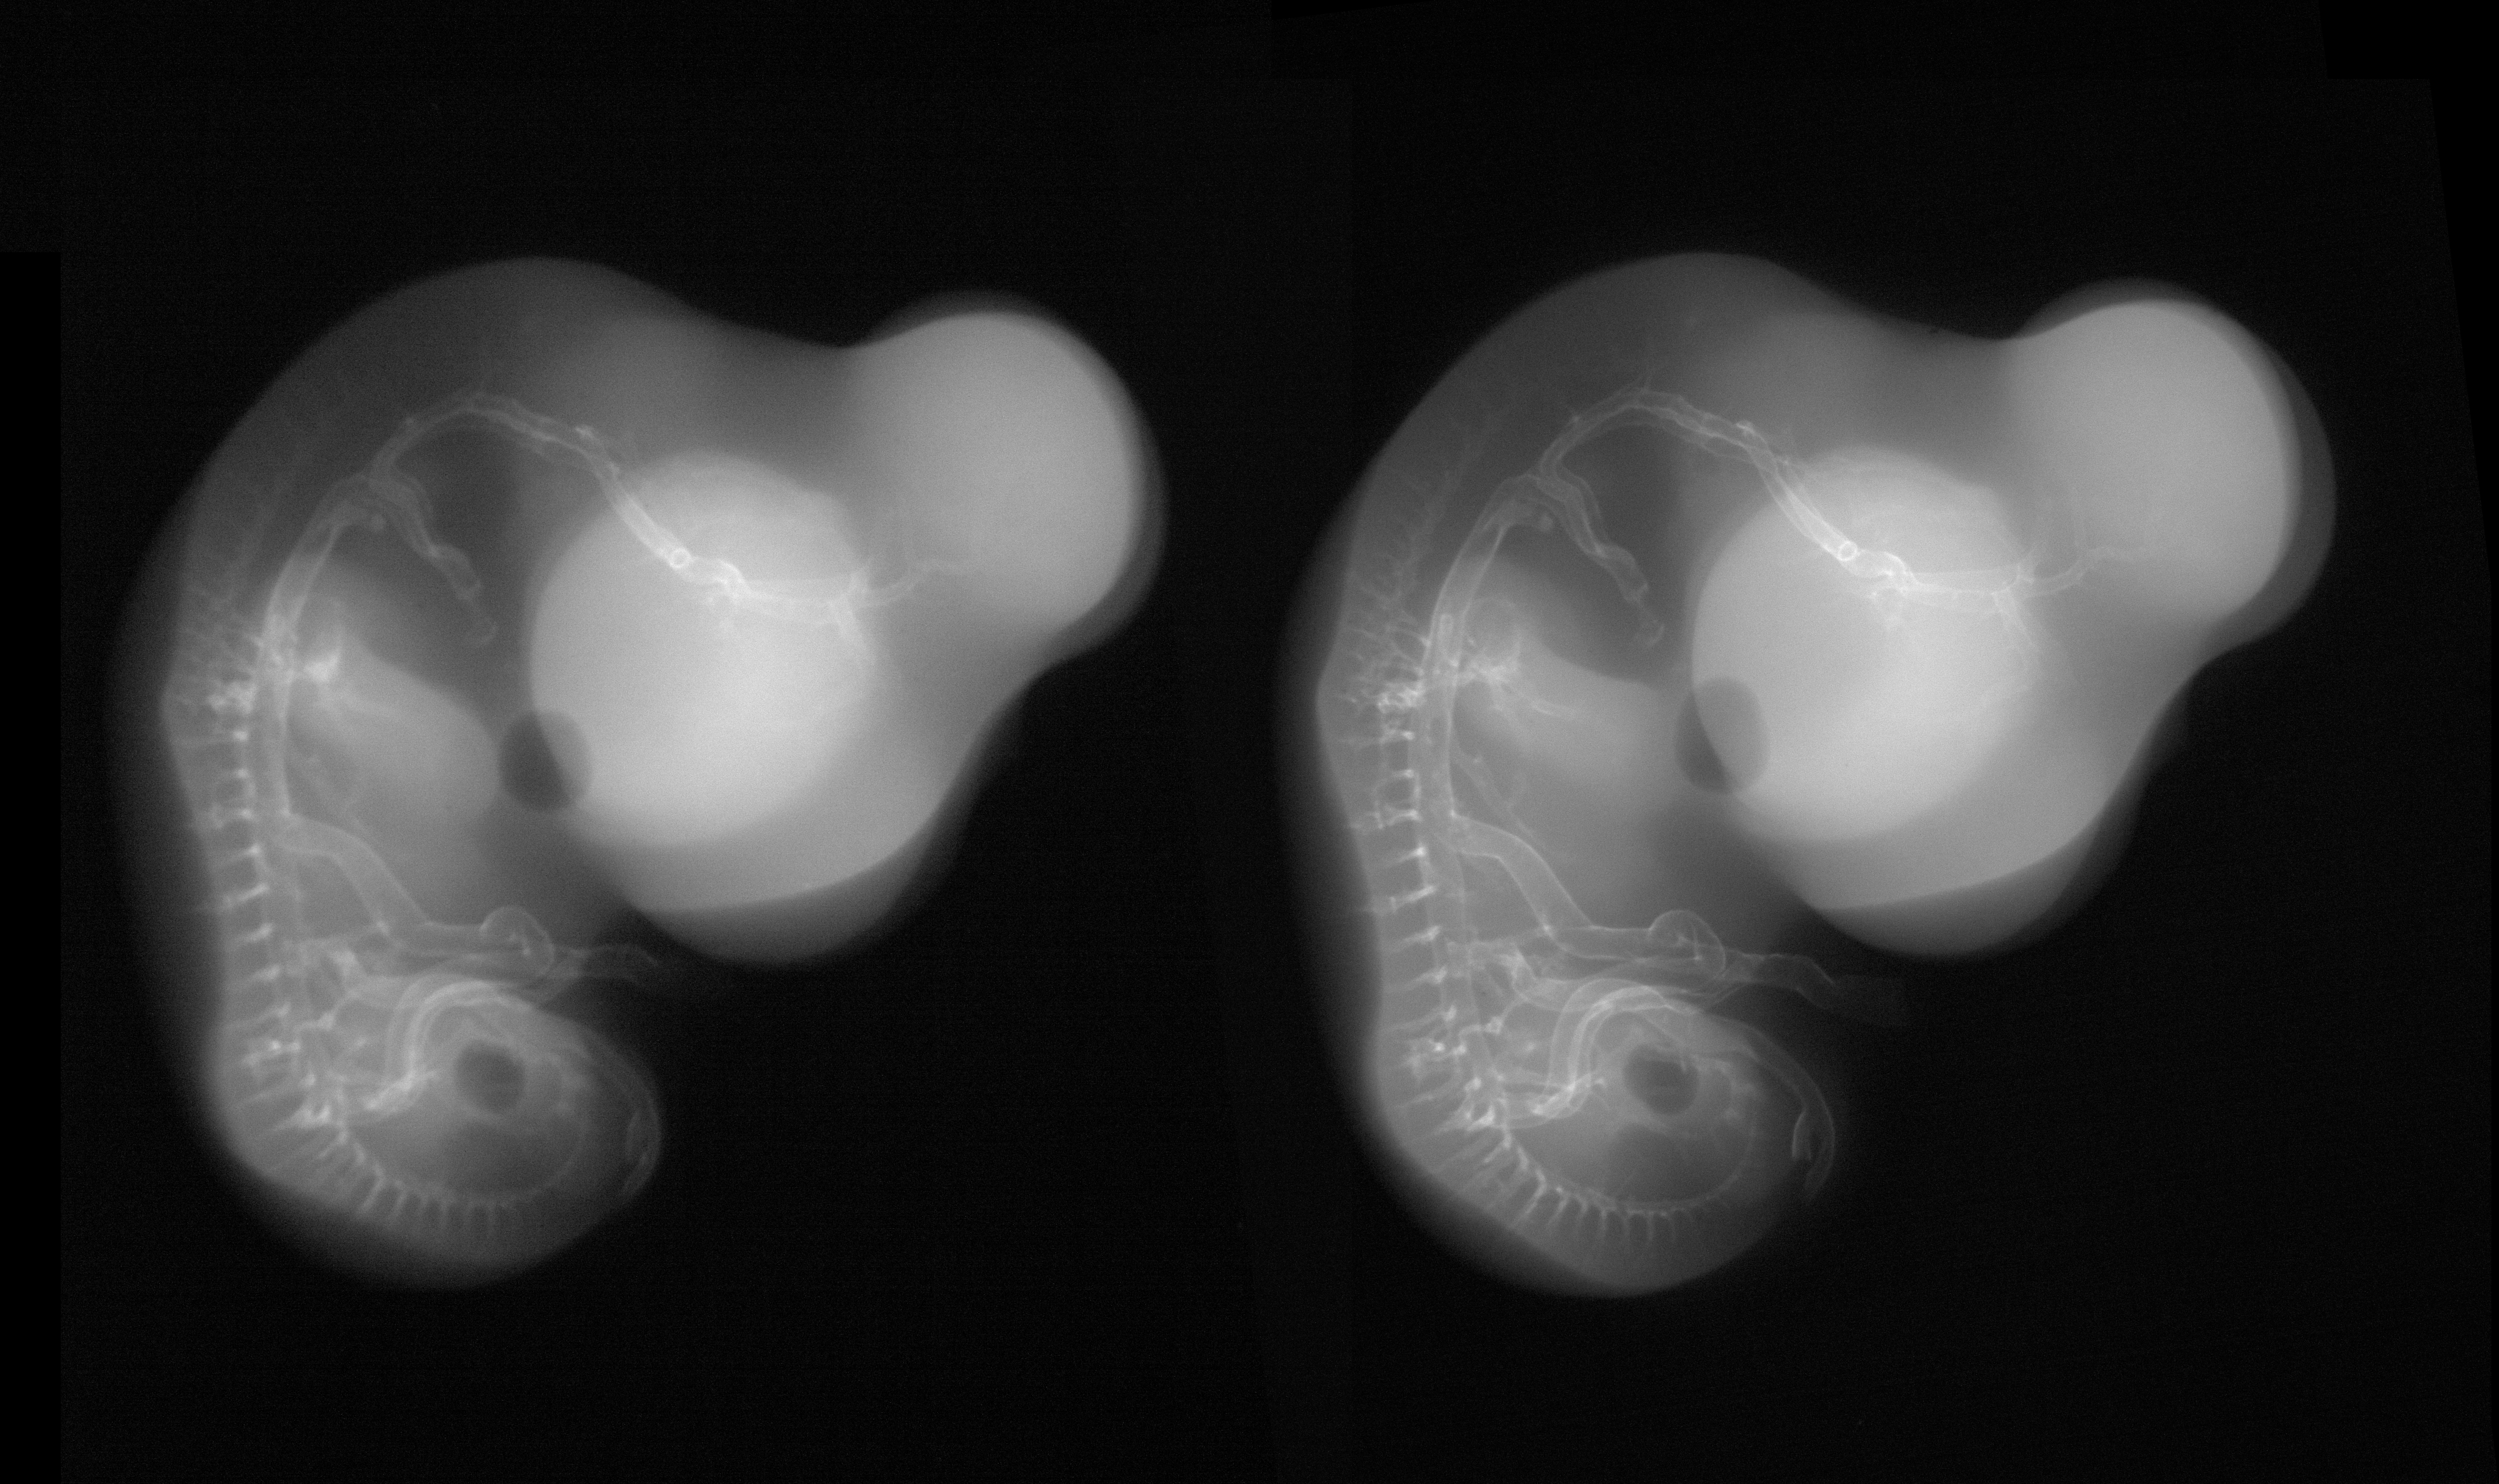

Chick Embryo Microangiography

Hamburger-Hamilton (HH) Stage 28 (approx. 5.5 - 6 days)

Stereo X-Ray Micrographs